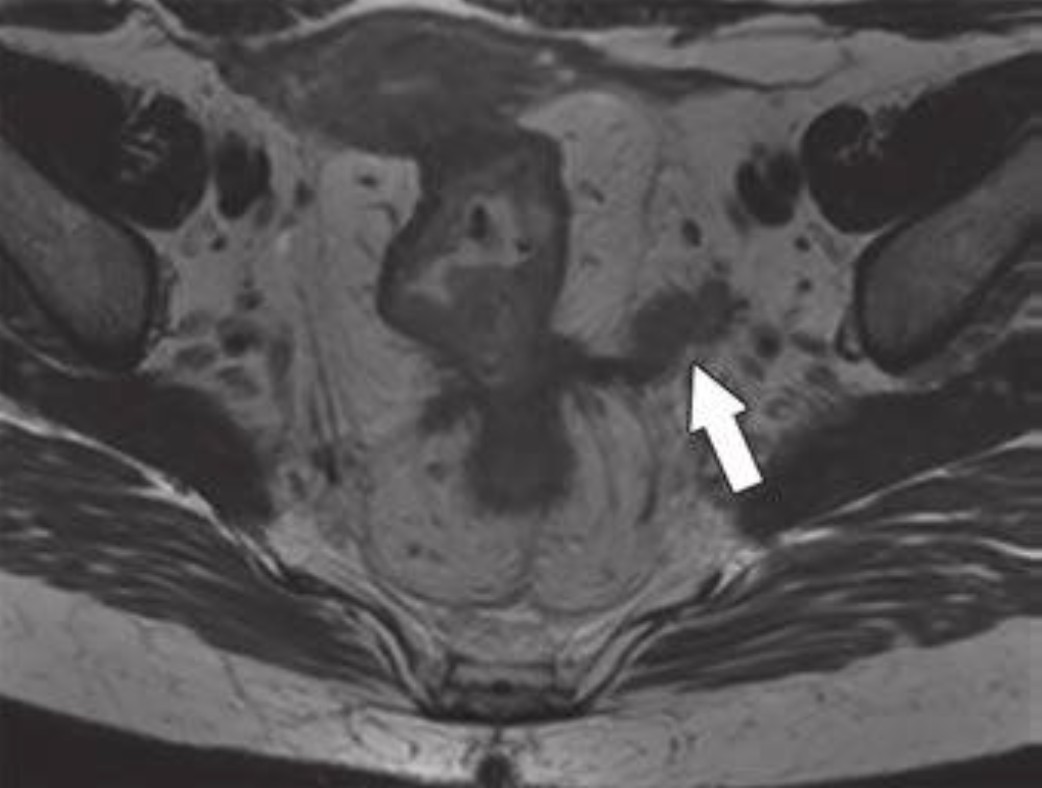

Rectal MRI unites American, Australian, and New Zealander abdominal imagers Read more